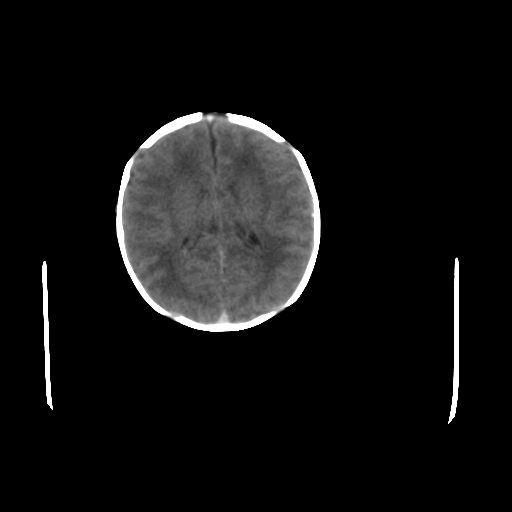

男,12天,自然分娩,其母发现右顶部头皮包块逐渐增大。

疑问:患儿脑白质密度比较低,基底节区密度比较高,类似于“双圈征”脑沟密度也偏高。该婴儿可有别的异常吗?反射正常吗?评分能达到5分吗?如果正常,就随诊观察吧。不正常要考虑到缺血缺氧性脑病。

鉴别:骨膜下血肿,一般为产伤,应用产钳之类的吧